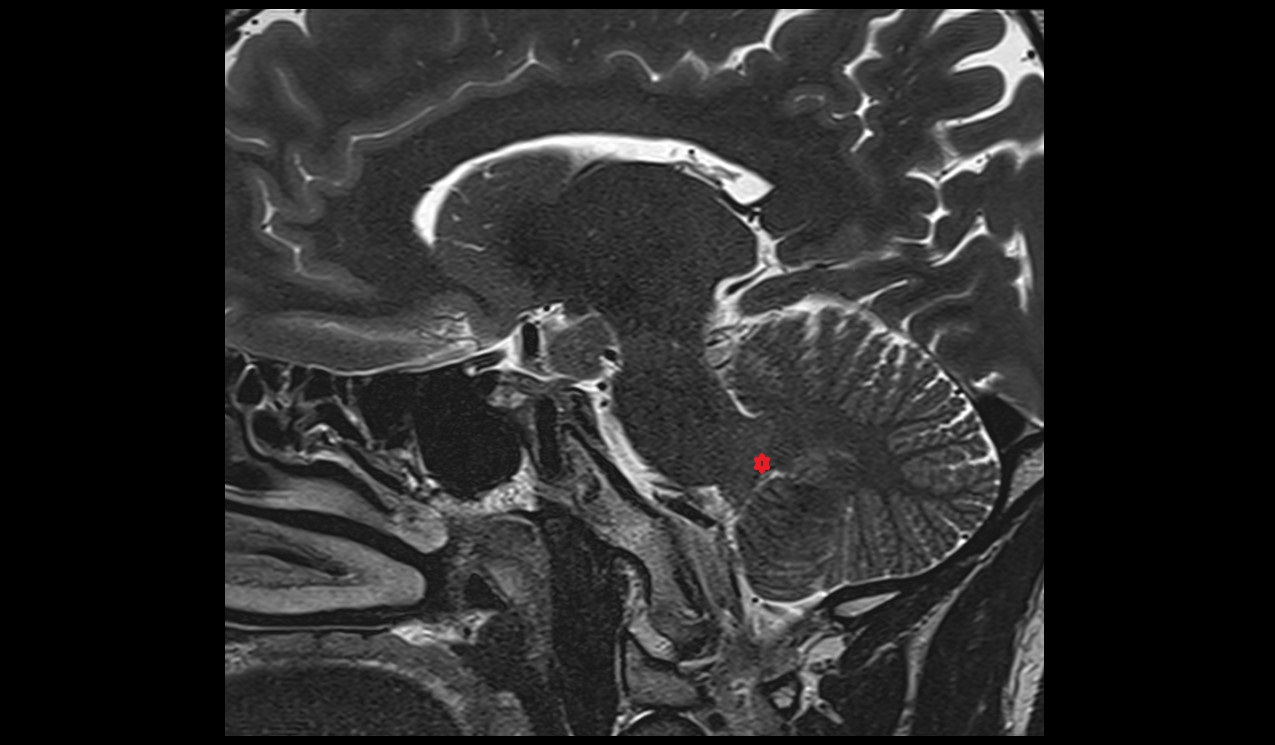

- Cerebellum

- Superior medullary velum

- Tonsil of cerebellum